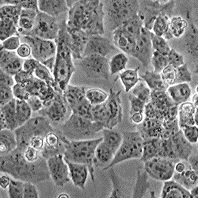

HuTu 80

Морфология: эпителиоподобная

Способ культивирования: монослойный